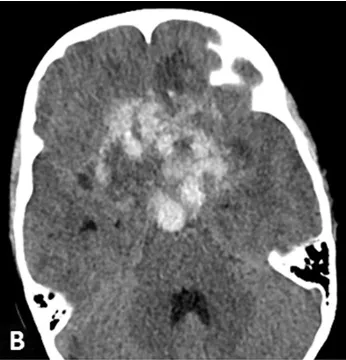

然而,9个月后,男孩在一次醒来时发现左眼看不见了。去医院检查确定左眼失明,且CT扫描显示肿瘤内部出血。患者继续采取保守治疗,但2周后病情恶化,出现严重头痛和昏迷。CT扫描显示肿瘤内部、左额叶和脑室内大量出血,伴有脑积水和弥漫性脑肿胀(图B)。